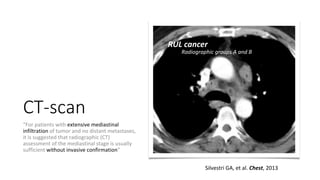

“For patients with extensive mediastinal

infiltration of tumor and no distant metastases,

it is suggested that radiographic (CT)

assessment of the mediastinal stage is usually

sufficient without invasive confirmation”

RUL cancer

Radiographic groups A and B